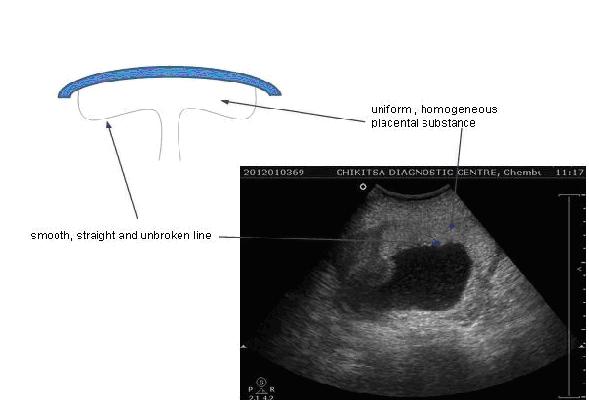

Grade - 0

Late 1st trimester-early 2nd trimester

Chorionic plate - Smooth, straight and well defined unbroken dense line.

Placental substance - Uniform homogeneous echotexture with out any echogenic areas

Basal layer - No basal layer echogenicities